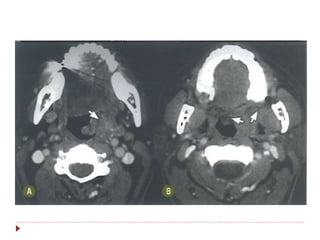

 Do osso hioide ao esôfago cervical.

 Três áreas de interesse:

 Seio piriforme (65%).

 Região pós-cricoide

 Parede posterior

 Os linfáticos drenam para cadeia

jugular e cruzam para o lado

contralateral (II, III, V e

retrofaríngeos).

 Sintomas: disfagia, rouquidão,

dispneia.

 Patologia: CEC.

Hipofaringe  Do ossohioide ao esôfago cervical.  Três áreas de interesse:  Seio piriforme (65%).  Região pós-cricoide  Parede posterior  Os linfáticos drenam para cadeia jugular e cruzam para o lado contralateral (II, III, V e retrofaríngeos).  Sintomas: disfagia, rouquidão, dispneia.  Patologia: CEC.